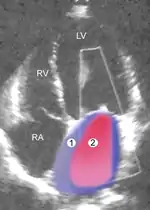

|

|

| Severe MR | Legend |

| 1 Left atrium (LA) – 2 MR Jet, LV Left ventricle – RV Right ventricle – RA Right atrium | |

An echocardiogram is commonly used to confirm the diagnosis of MR.[16] Color doppler flow on the transthoracic echocardiogram (TTE) will reveal a jet of blood flowing from the left ventricle into the left atrium during ventricular systole. Also, it may detect a dilated left atrium and ventricle and decreased left ventricular function.[6] A transesophageal echocardiogram can give clearer images if needed as the back of the heart can also be viewed.[17]